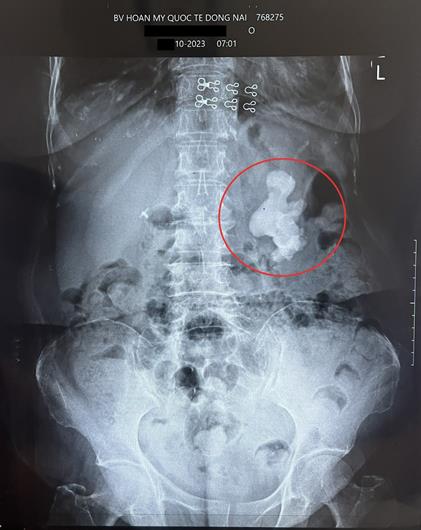

Khối sỏi “khổng lồ” trong thận trái cụ bà qua phim chụp

Cụ bà nhập viện trong tình trạng đau âm ỉ hông lưng trái, đau từng cơn kèm tiểu buốt tái diễn nhiều lần. Qua thăm khám, bác sĩ phát hiện cụ H. có sỏi san hô phức tạp, tái phát ở thận trái, kích thước lớn, cần phẫu thuật kịp thời để tránh nguy cơ biến chứng.

BS CKI Bùi Khắc Thái, phẫu thuật viên chính cho biết, đây là ca bệnh rất phức tạp do người bệnh đã cao tuổi, lại mắc bệnh cao huyết áp, 10 năm trước từng mổ hở lấy sỏi cùng bên thận trái. Nguy cơ chảy máu, dính và khó bóc tách trong quá trình phẫu thuật rất cao. Đặc biệt, trường hợp này là ca bệnh sỏi tái phát, sỏi phân bố nhiều nhánh cài vào các đài thận, lấp đầy ở cả 3 đài thận trái của người bệnh, gây ứ nước độ 1.